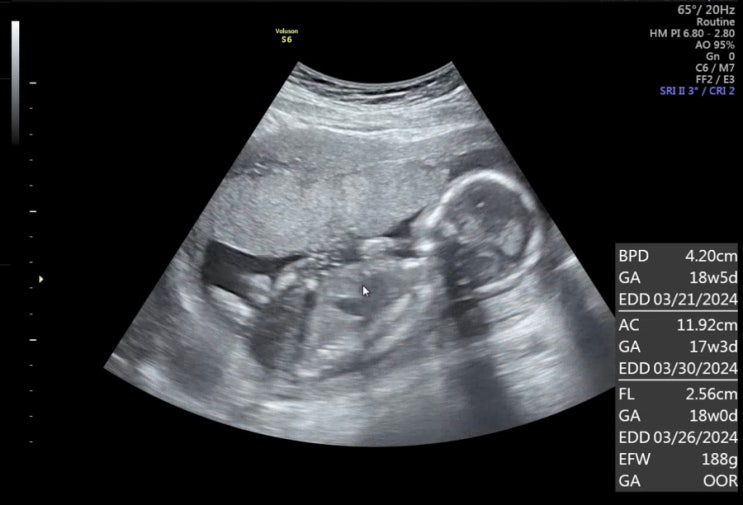

3월 13일 수요일, 37주 2일차 검진 이제 일주일에 한번씩 검진가야한다..! 가자마자 또 태동검사를 했는데 ...